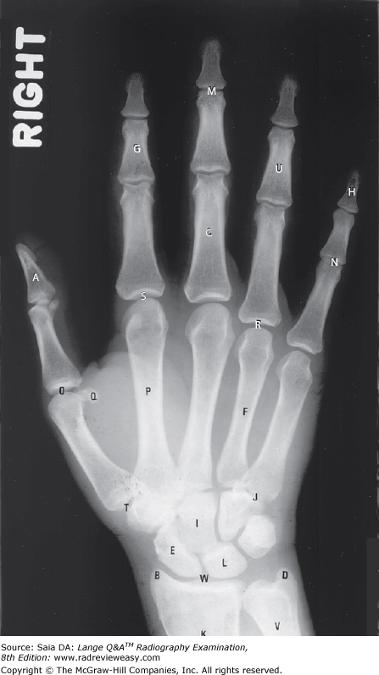

Which of the following correctly identifies the letter T in the radiograph shown in Figure 7–13?

Diarthrotic joint

Which of the following correctly identifies the letter L in the radiograph shown in Figure 7–13?

Lunate

What is the structure labeled number 2 in Figure 2–37?

Trapezium

Which of the following correctly identifies the radial styloid process in the illustration in Figure A?

Number 11